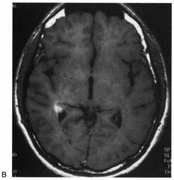

Fig. 15. Bilateral incomplete hemianopia. A 69-year-old man with decreased vision after prostate surgery. A. Fields show remaining central parafoveal vision with some sparing of inferior left quadrant. Note how the defect respects the vertical meridian. B. MRI shows bilateral medial occipital infarction, with sparing of the occipital poles, accounting for the macular-sparing bilaterally. (Courtesy of Dr. Lucia Vaina.)